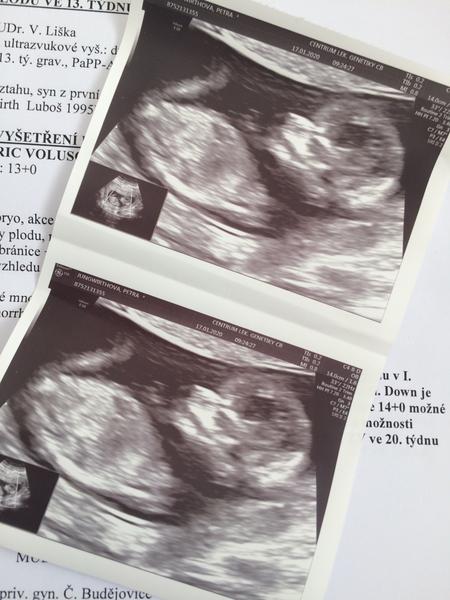

Holky, jdu se pochlubit. Dneska na genetice vše v pořádku, mimi má 6,7cm a odpovídá 13tt+O vše negativní a na 85% chlapeček 🥰🥰🥰 Pindíka jsem viděla ještě dřív než nám to řekla paní doktorka řekla 😂